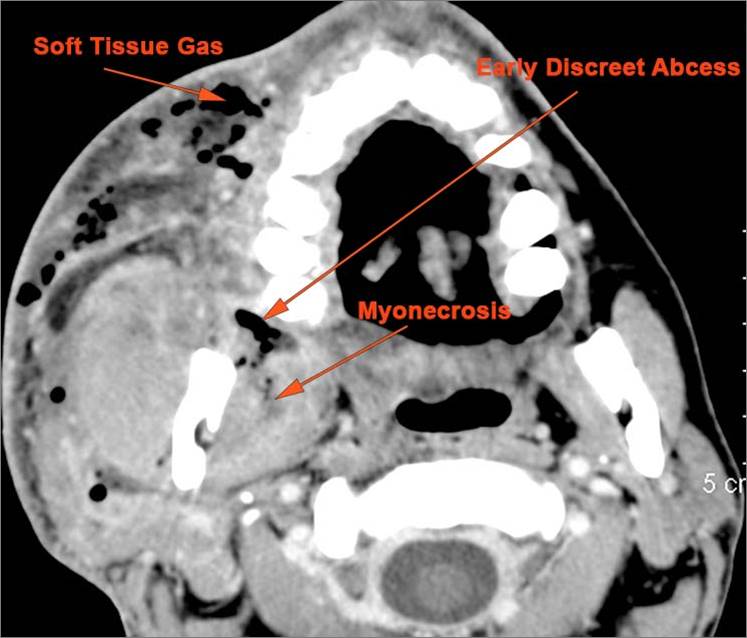

There is gas in the soft tissues. [Yes/No]

There is edema/abscess within or surrounding the buccal space, masticator space, floor of the mouth, submandibular space or the adjacent superficial fascia or subcutaneous fat and skin. [Yes/No]

Deep neck cellulitis [with/without] abscess.